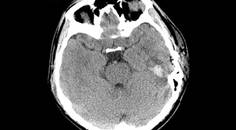

Challenge Case Report: PostCOVID-19 Encephalitis

Meghan Grassel, MS; Abdul R. Alchaki, MDMeghan Grassel, MS; Abdul R. Alchaki, MD - MS & Immune Disorders